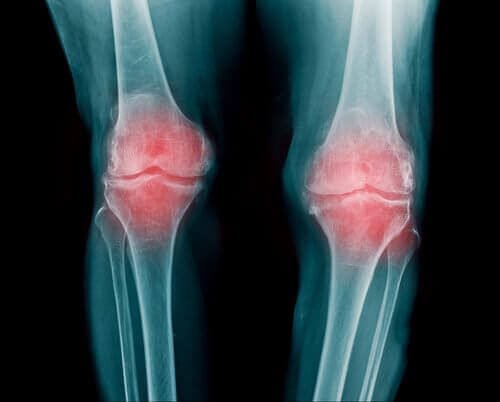

As articulações estão nas extremidades ósseas do corpo, são responsáveis por proteger os côndilos e desempenham um papel fundamental no movimento das extremidades inferiores e superiores.

Entre cada articulação há um segmento de cartilagem, que evita o atrito dos ossos entre si. No entanto, a passagem do tempo causa um desgaste gradual, o que gera dor e inflamação.

Deve-se saber que a dor presente é decorrente do processo inflamatório, e não da degeneração do tecido. No entanto, o inchaço é a principal reação ao desgaste celular.